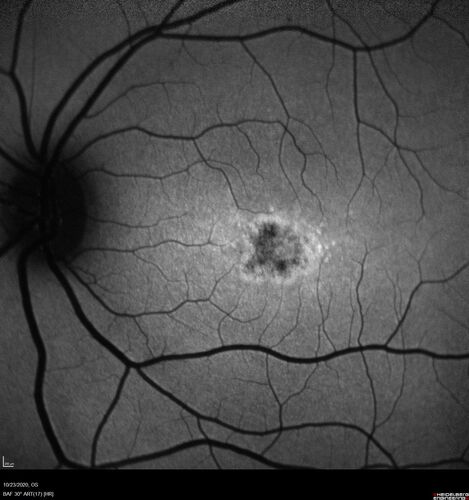

25 year old with Stargard and 2 ABCA4 mutations.

She has worn glasses since she was a kid.  Since she became an adult her vision started to deteriorate more rapidly.  This seems to have been happening since she entered the accounting department for the last two years.  Her vision is worse in the light especially when she is driving.  She can see green lights in the night but not in the day.  She sees better on a dark background than on a light background.  Her mom is genetically visually impaired with Stargardts.  Her father has RP.  The mother was genetically tested in Boston about 23 years ago.  That was when the gene was first being isolated. (The mother has seven brothers and sisters and four have stargardts and they are legally blind.  Also one cousin has it.)

VA OD: Dcc20/160-1 PH20/80 Ncc20/200-2

VA OS: Dcc20/160-2 PH20/80-1 Ncc20/200-1

IOP: TP: OD:20 OS:21